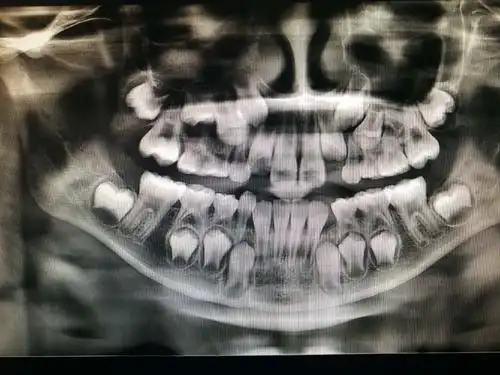

如何看牙科的x光片?牙片详解,教你看懂牙片!

拍的牙片

拍牙片前你需要知道的二三事

给大家看看我的牙片

孕妇可能不得不在宝宝出生前拍牙片,因为未经治疗的牙科感染会对胎儿